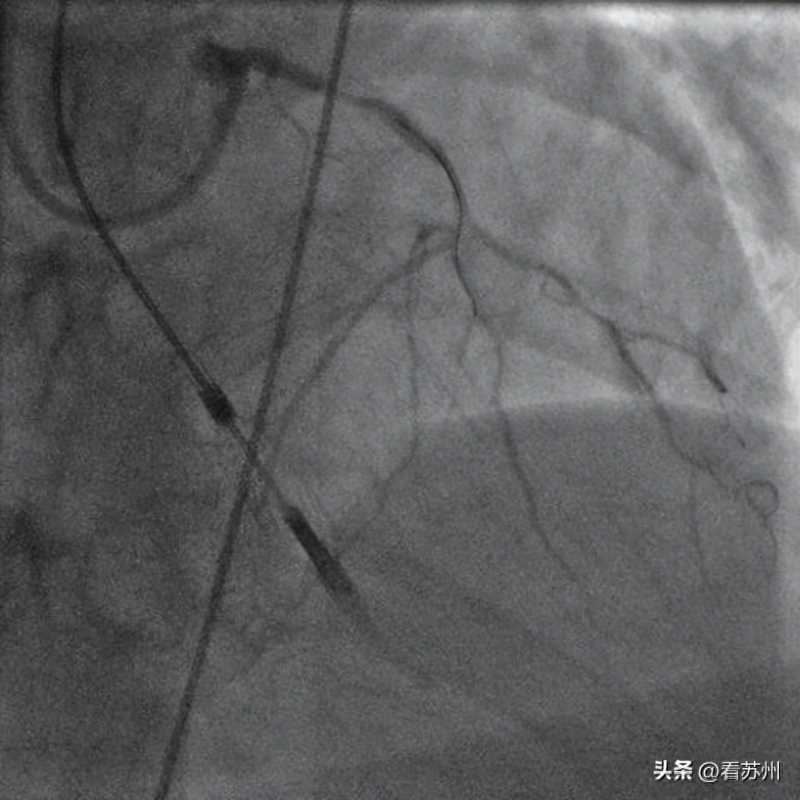

复旦大学附属中山医院葛均波院士团队成功在新一代介入泵(心擎医疗)支持下为一名男性患者完成高风险经皮冠脉手术(HRPCI)。

本次高危PCI手术的顺利开展,初步证实了心擎医疗的新一代介入泵在辅助高危PCI手术中的安全性和有效性,代表世界最小介入式人工心脏正式迈向临床,具有重要意义。

患者为一名48岁的男性,手术前诊断为冠状动脉粥样硬化性心脏病、心力衰竭、冠脉支架植入后、II型糖尿病。

患者既往冠脉三支病变、左主干病变伴前降支慢性完全闭塞病变,术前评估左心室射血功能差,病程复杂,手术风险高。

“经过评估,我们认为患者在手术过程中,可能会发生血流动力学障碍,需在机械循环辅助下进行手术,经家属同意后决定使用新一代介入泵循环支持下开展PCI手术。”葛均波院士接受记者采访时说。

“术后介入泵顺利回撤至鞘内撤出,仅使用单把血管缝合器就完成了股动脉穿刺处止血,患者6小时后即下床活动,无血管并发症。”葛均波说,“手术是成功的。”